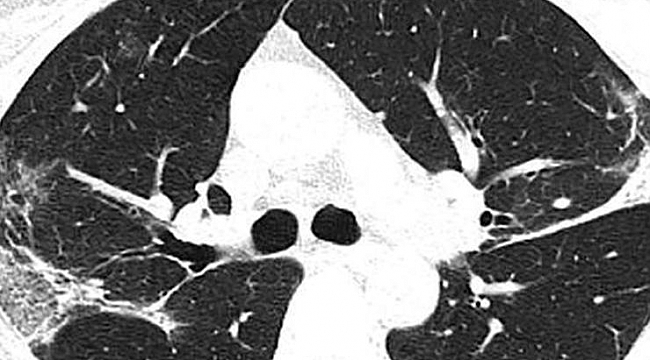

X-ray ışını taramalarında corona virüsün etkileği yerler beyaz olarak görülüyor. Uzmanlar, hastada virüsün akciğerlerdeki hava keseciklerini kısmen doldurduğunu ve akciğer nodüllerine sebep olduğunu belirtti. .Diğer taraftan aynı tip anormalliklerin SARS (Şiddetli Akut Solunum Sendromu) ve MERS (Ortadoğu Solunum Sendromu) vakalarında da görüldüğünü söylediler.

Wuhan'a seyahat ettikten sonra corona virüse yakalanan 54 yaşında bir kadının bilgisayarlı tomografi taramaları da akciğerlerinde hava boşluklarının kısmen dolduğunu gösteriyor.